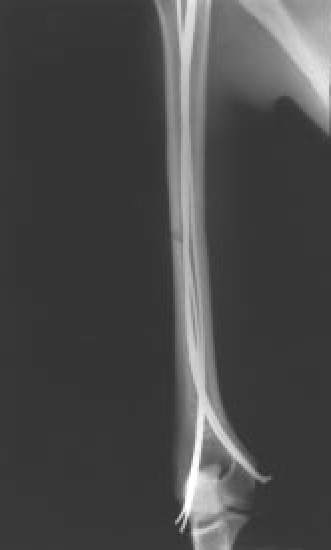

Fig. 3B.: Control postoperatorio, tras osteosíntesis intramedular elástica